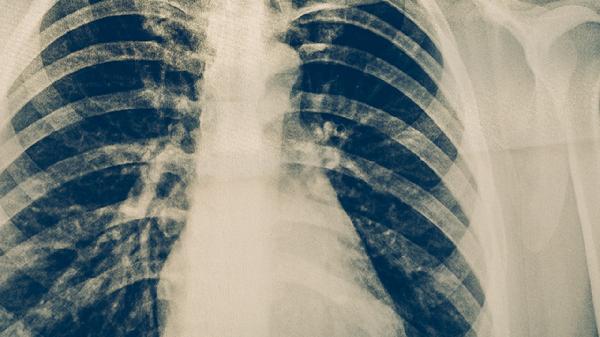

肺结核治愈后是否影响体检主要取决于治愈标准是否达标。痰涂片或培养连续多次阴性、胸部影像学显示病灶稳定钙化、完成规定疗程且停药后随访复查无复发迹象,即符合临床治愈标准。此类情况下体检机构通常不会因既往肺结核史直接判定不合格,但可能要求提供出院小结、复查胸片等医学证明。部分特殊职业如食品加工、幼教等可能需额外提交疾控中心开具的康复证明。

若治愈时间较短或存在病灶未完全吸收的情况,体检可能被要求延期。部分单位体检标准较严格时,可能要求治愈后观察1-2年无异常才予通过。活动性肺结核未治愈或存在耐药结核病史者,体检通常无法通过。体检前建议携带完整的治疗记录、近期胸部CT报告及痰检结果,必要时可提前与体检机构沟通确认具体要求。